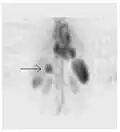

-

A nuclear medicine SPECT liver scan with technetium-99m labeled autologous red blood cells. A focus of high uptake (arrow) in the liver is consistent with a hemangioma. -